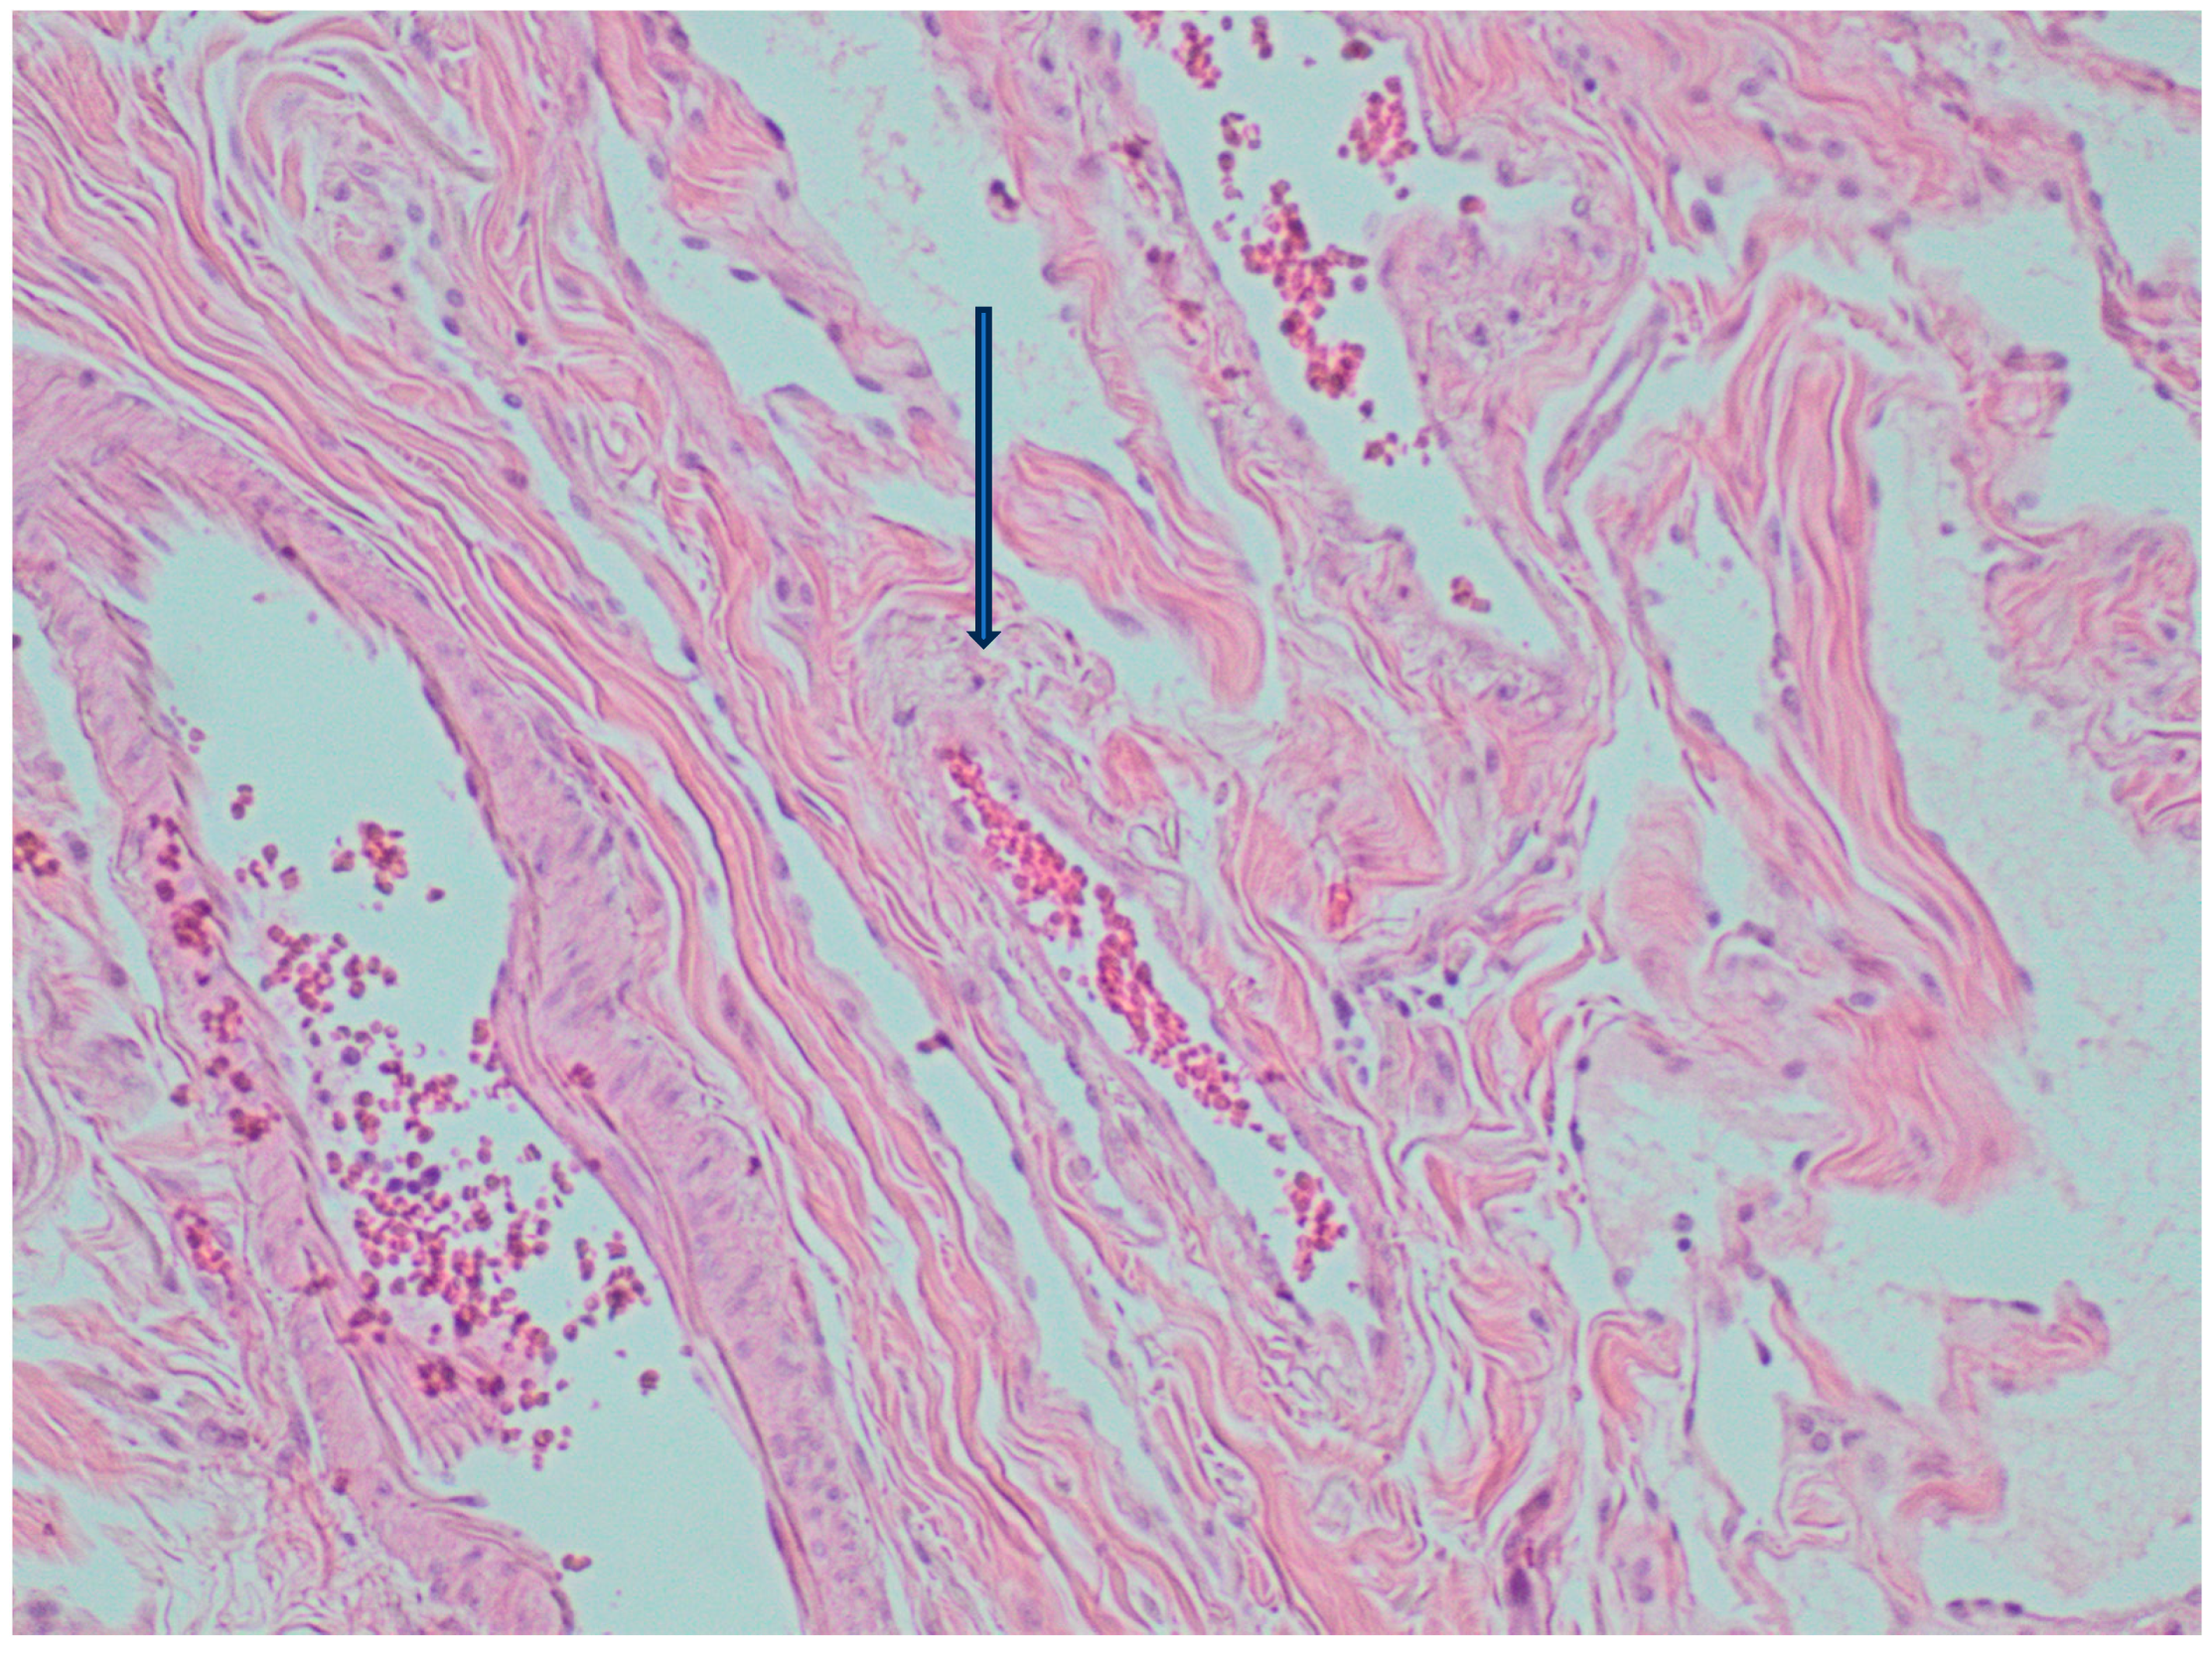

2. Case Presentation